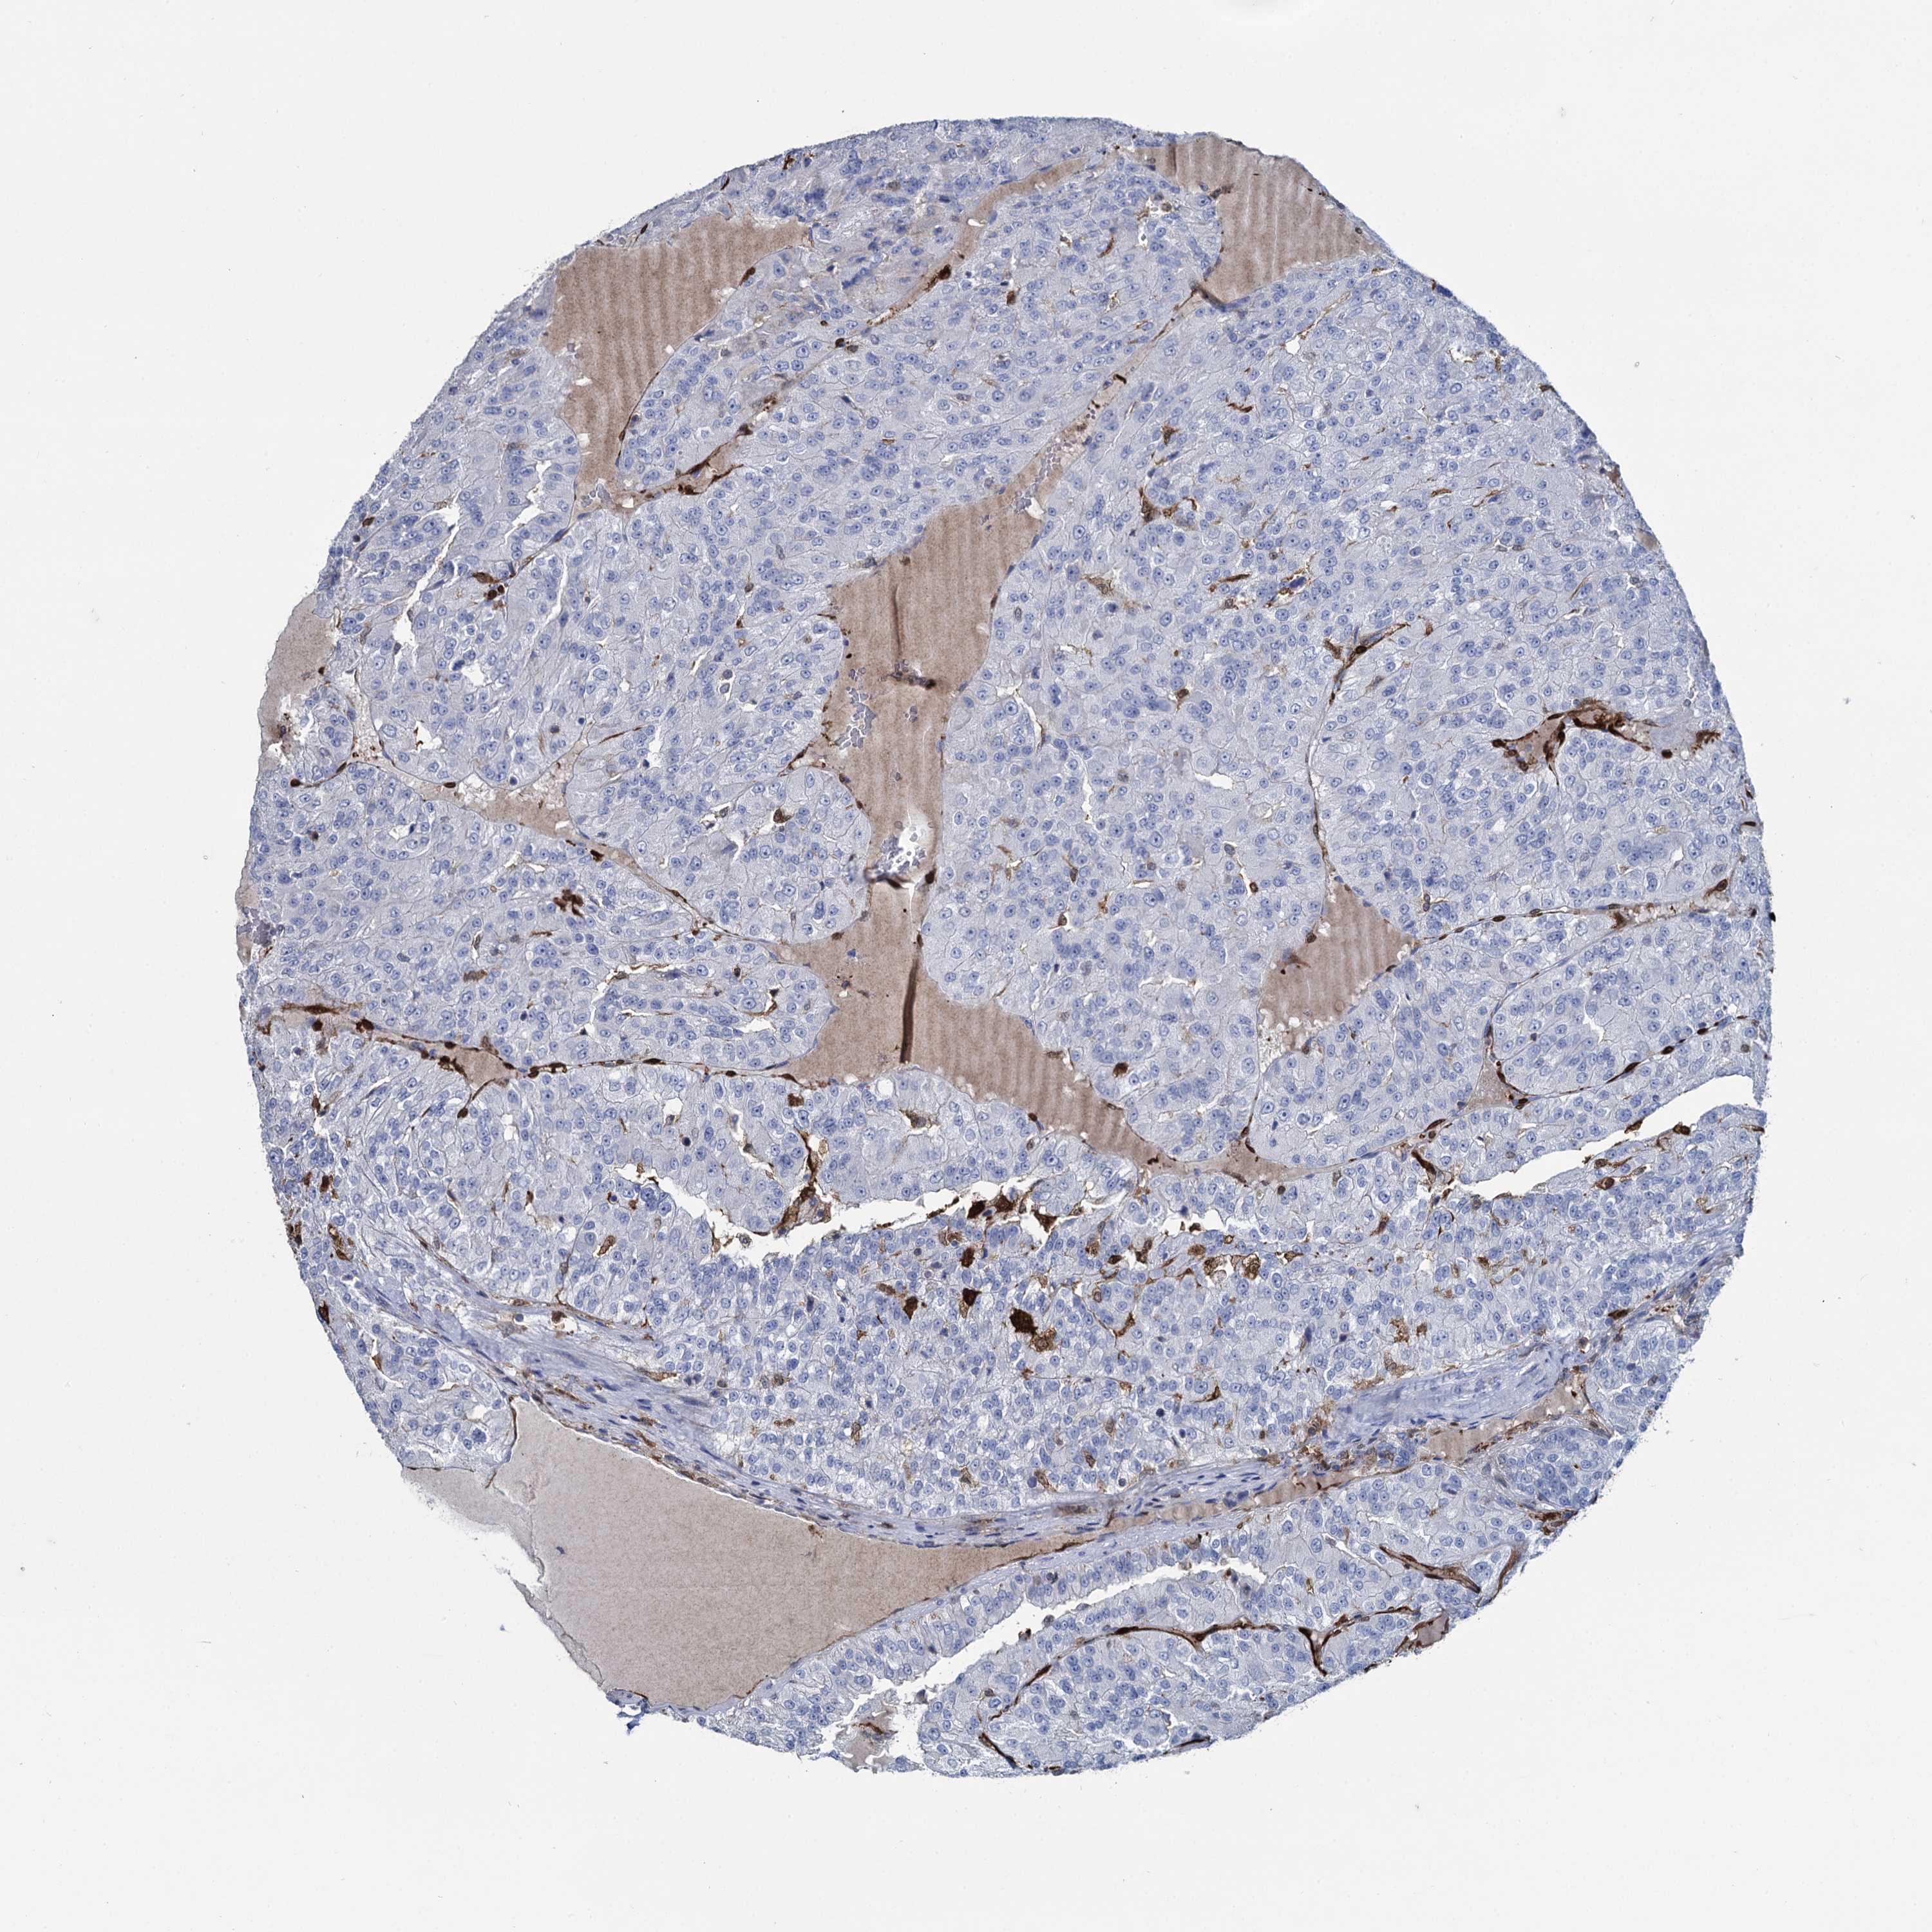

Renal cancer

Kidney renal clear cell carcinoma

KIDNEY RENAL CLEAR CELL CARCINOMA (VALIDATION) - Interactive survival scatter ploti

The Survival Scatter plot shows the clinical status (i.e. dead or alive) for all individuals in the patient cohort, based on the same data that underlies the corresponding Kaplan-Meier plots. Patients that are alive at last time for follow-up are shown in blue and patients who have died during the study are shown in red.

The x-axis shows the expression levels (FPKM) of the investigated gene in the tumor tissue at the time of diagnosis. The y-axis shows the follow-up time after diagnosis (years). Both axes are complimented with kernel density curves demonstrating the data density over the axes. The top density plot shows the expression levels (FPKM) distribution among dead (red) and alive patients (blue). The right density plot shows the data density of the survived years of dead patients with high and low expression levels respectively, stratified using the cutoff indicated by the vertical dashed line through the Survival Scatter plot. This cutoff is automatically defined based on the FPKM cutoff that minimizes the p-score. The cutoff can be changed by dragging the vertical line or by entering a cutoff value in the square labeled "Current cut-off".

Under the Survival Scatter plot the p-score landscape (black curve; left axis) is shown together with dead median separation (red curve; right axis). Dead median separation is the difference in median mRNA expression between patients who have died with high and low expression, respectively. It is calculated as follows: median FPKM expression of dead patients with high expression - median FPKM expression of dead patients with low expression. This is intended to aid the user in visually exploring custom cutoffs and the associated p-scores and dead median separation.

Individual patient data is displayed and can be filtered by clicking on one or more of the category buttons on the top of the page. Categories describing expression level and patient information include: high, low, alive, dead, female, male and tumor stages. The scale of the x-axis can be toggled between linear and log-scale by clicking on the "x log" button. Mouse-over function shows TCGA ID, patient information and mRNA expression (FPKM) for each patient.

& Survival analysisi

Kaplan-Meier plots summarize results from analysis of correlation between mRNA expression level and patient survival. Patients were divided based on level of expression into one of the two groups "low" (under cut off) or "high" (over cut off). X-axis shows time for survival (years) and y-axis shows the probability of survival, where 1.0 corresponds to 100 percent.

FABP5 is validated prognostic, high expression is unfavorable in Kidney Renal Clear Cell Carcinoma (validation)

Best expression cut offi

: 106.1

Average pTPM 98.5

Number of samples 100